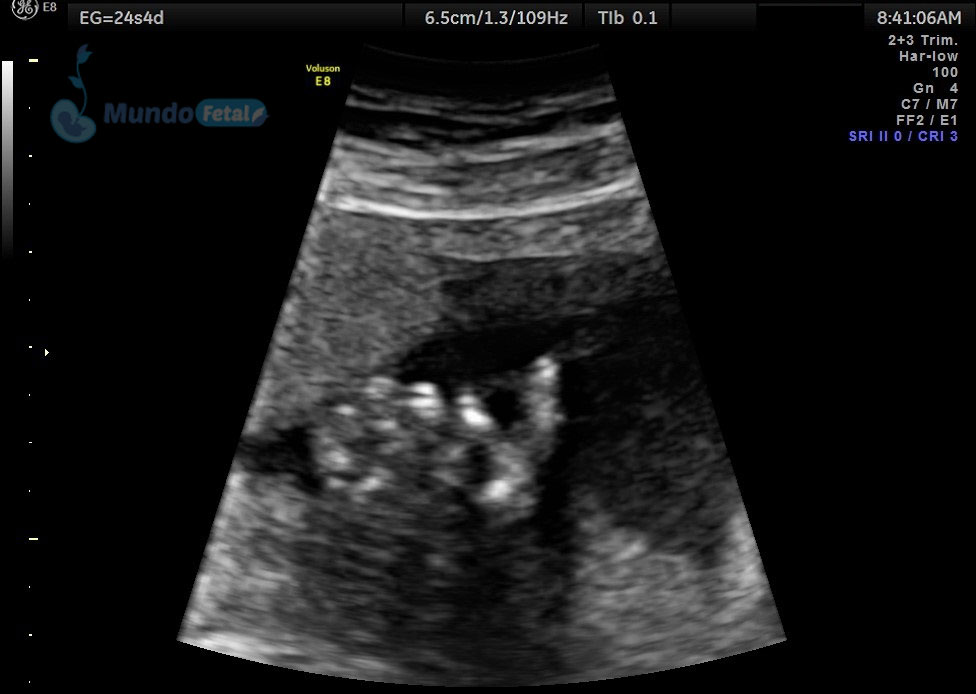

ANATOMICO-VEJIGA